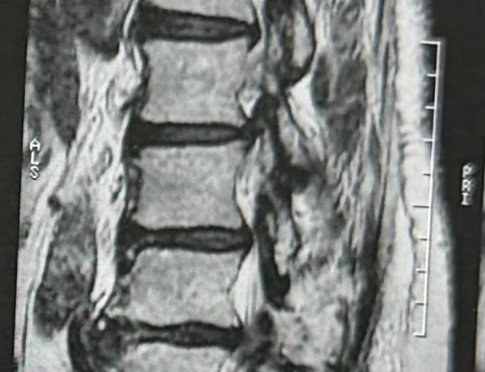

A hérnia de disco ocorre quando uma parte do disco intervertebral — uma espécie de “amortecedor” entre as vértebras — se desloca e começa a comprimir os nervos. Essa compressão gera dor intensa, formigamento, perda de força e, em alguns casos, até dificuldade para andar. É uma condição extremamente comum e pode afetar desde jovens com sobrecarga na coluna até adultos com desgaste natural.

A dor da hérnia de disco ocorre porque o material interno do disco — chamado núcleo pulposo — escapa e irrita as raízes nervosas. Quando isso acontece, o paciente pode sentir dor que “desce” para a perna (ciatalgia), ou para o braço, no caso da região cervical. Quanto maior a compressão, maiores tendem a ser os sintomas neurológicos.